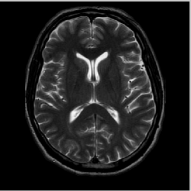

V-C Comparisons With State-of-the-Art Algorithms

We compare the proposed scheme with classical local total variation algorithm and the dictionary learning MRI (DLMRI) scheme [23]. The DLMRI method is also a patch based regularization scheme, where a dictionary is learned from the patches in the image. This scheme was reported [23] to provide considerably better reconstructions than the sparse recovery algorithm combining wavelet and TV regularization [24]. We relied on the MATLAB implementation of DLMRI222The DLMRI code is available on the author’s website www.ifp.illinois.edu/ yoram/DLMRI-Lab/DLMRI.html. A key difference with the results reported in [23] is that we used the complex version of the code distributed by the authors. This was required to make the comparisons fair to TV and our non-local implementations as both of them do not use this constraint. Note that this assumption is often not satisfied in routine MRI exams.

The comparison of the methods in the context of random sampling with 20% of the samples retained in the absence of noise is shown in Fig. 4. The regularization parameters of all the algorithms have been optimized to yield the best signal to noise ratio (SNR). The SNR and the peak SNR (PSNR) that are used for the comparisons in this paper are computed as

We observe that the proposed non-local algorithm provides better preservation of edge details and minimize patchy artifacts as seen in TV reconstructions. The quantitative comparisons of different methods on more MR images in the absence of noise using 5 fold random sampling operator are reported in Table III. We observe that the NLS scheme provides a consistent 2-4 dB improvement over the other methods in most cases.

Refer to caption

(a) Original

(b) DLMRI, SNR=20.46

(c) TV, SNR=22.80

(d) NLS, SNR=28.41

(e) Sampling pattern

(f) DLMRI error

(g) TV error

(h) NLS error

Figure 4: Comparison of the algorithms in the absence of noise. We consider the recovery of a 256×\times256 MRI brain image from 20% of its Fourier samples, acquired using a random sampling pattern shown in (e) using non-local shrinkage scheme (NLS), DLMRI and local TV (TV). The reconstructions are shown in (b)-(d). The corresponding error images, scaled by a factor of 5 for better visualization, are shown in the bottom row. The reconstructions show that the NLS scheme is capable of better preserving the edges and details, resulting in less blurred reconstructions.